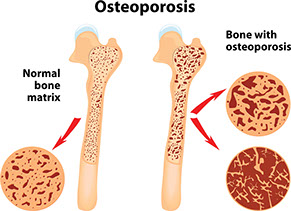

Osteoporosis

Signs & Symptoms

Leg or ankle pain with gradual loss of height; stooped posture; backache; and/or past bone fractures, especially in the wrists and hips.